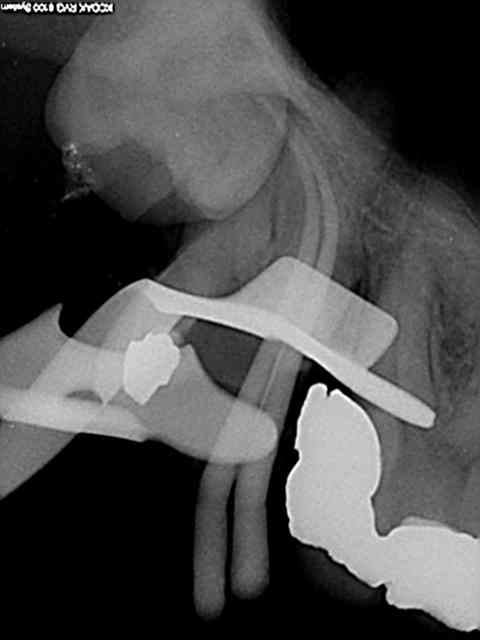

plus d'une heure pour essayer de sauver ces 37 et 38...

mais etait ce vraiment suffisant? cicatrisation possible?